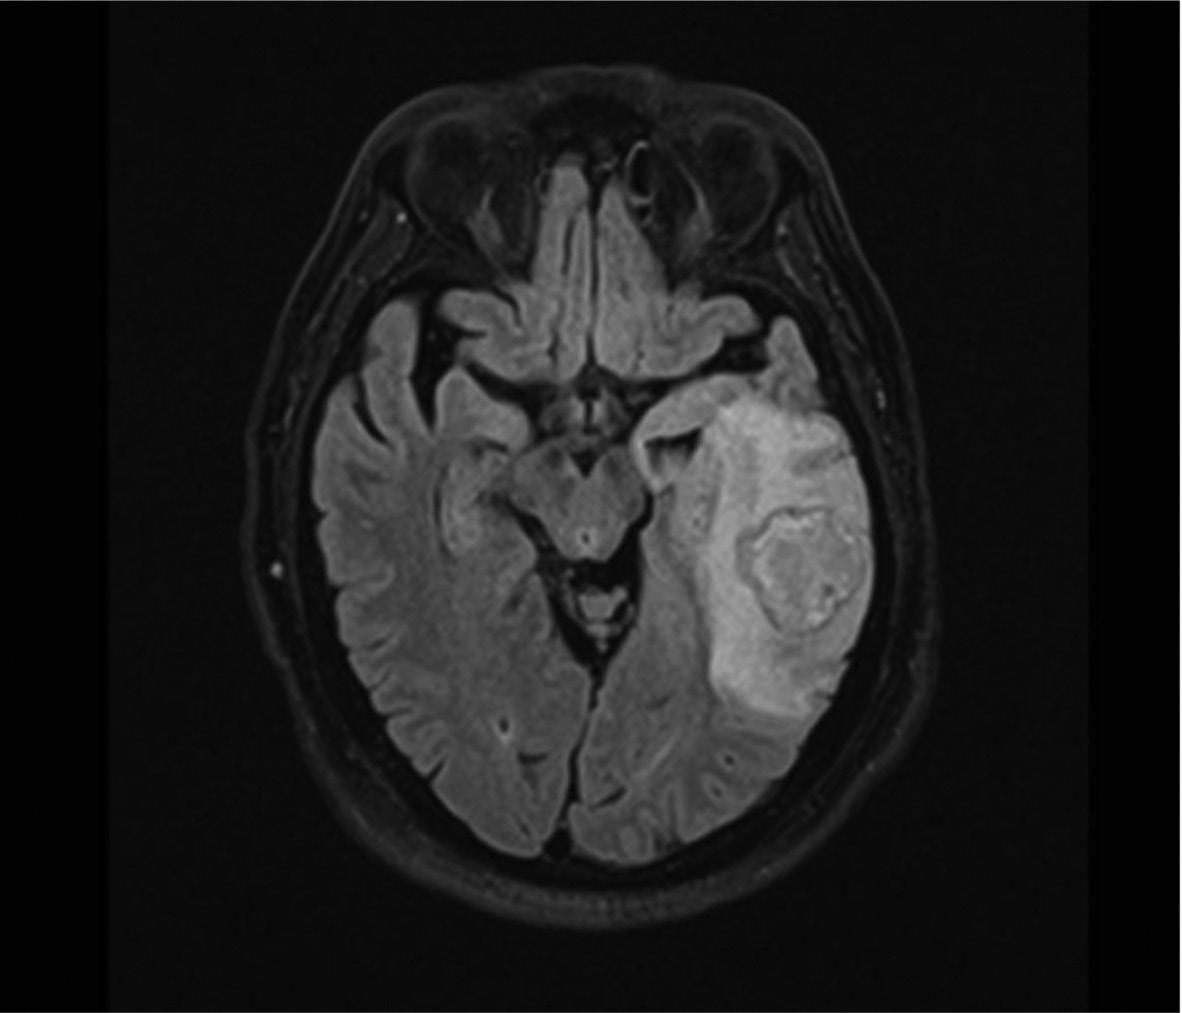

Resultados: Presencia de una lesión intraaxial a nivel parietal y temporal izquierdo.

Methods: Simple MRI and with intravenous (IV) contrast. Results: Presence of an intraaxial lesion in the left parietal and temporal area.

Al llegar a urgencias del hospital de tercer nivel se le realizaron exámenes de laboratorio que mostraron leucocitosis (15.22 K/μL) a expensas de neutrófilos, proteína C reactiva de alta sensibilidad elevada (9.08 mg/L) y velocidad de sedimentación globular elevada (57 mm/hr), procalcitonina negativa. También a la llegada, se le realizó una RM de cráneo simple (Fig. 1). La cual evidenció la lesión, sin embargo, no ofreció información crítica, por parte del servicio de imagenología se sugirió realizar una RM de cráneo con contraste IV. Posteriormente realizó la RM de cráneo con contraste IV, y se reportó lo siguiente:

Presencia de una lesión intraaxial a nivel parietal y temporal izquierdo, que condiciona efecto de masa, con edema vasogénico, que oblitera la amplitud de surcos y cisuras hacia la convexidad, con desplazamiento de la línea media de 4 mm con asimetría ventricular por disminución de volumen del ventrículo lateral izquierdo. La lesión es redonda, de bordes microlobulados con halo hipointenso en secuencias ponderadas en T2 e hiperintensa en T1 con centro heterogéneo de predominio hiperintenso en T2 con diámetros de 3 x 2.8

Figura 1. Resonancia magnética de cráneo simple en secuencia T1. Lesión que abarca lóbulos parietal y temporal izquierdos con un centro hiperintenso con relación al líquido cefalorraquídeo.

Figura 2. Figura 2. Resonancia magnética de cráneo con secuencia de difusión ponderada (DWI). Lesión con realce en forma de anillo con difusión restrictiva.

Rev Med HC Soc Med Univ 2022;4(4):16-21

x 2.3 cm en sentido rostrocaudal, laterolateral y dorsoventral respectivamente, el cual muestra intenso reforzamiento predominantemente periférico. En la secuencia de difusión existe restricción homogénea focal central como también restricción difusa y continua cortical del lóbulo temporal con extensión a la región insular e hipocampo. Conclusión: cambios altamente compatibles con absceso parieto-temporal izquierdo con edema perilesional y efecto de masa asociado a cambios por cerebritis del lóbulo temporal (Fig. 2).